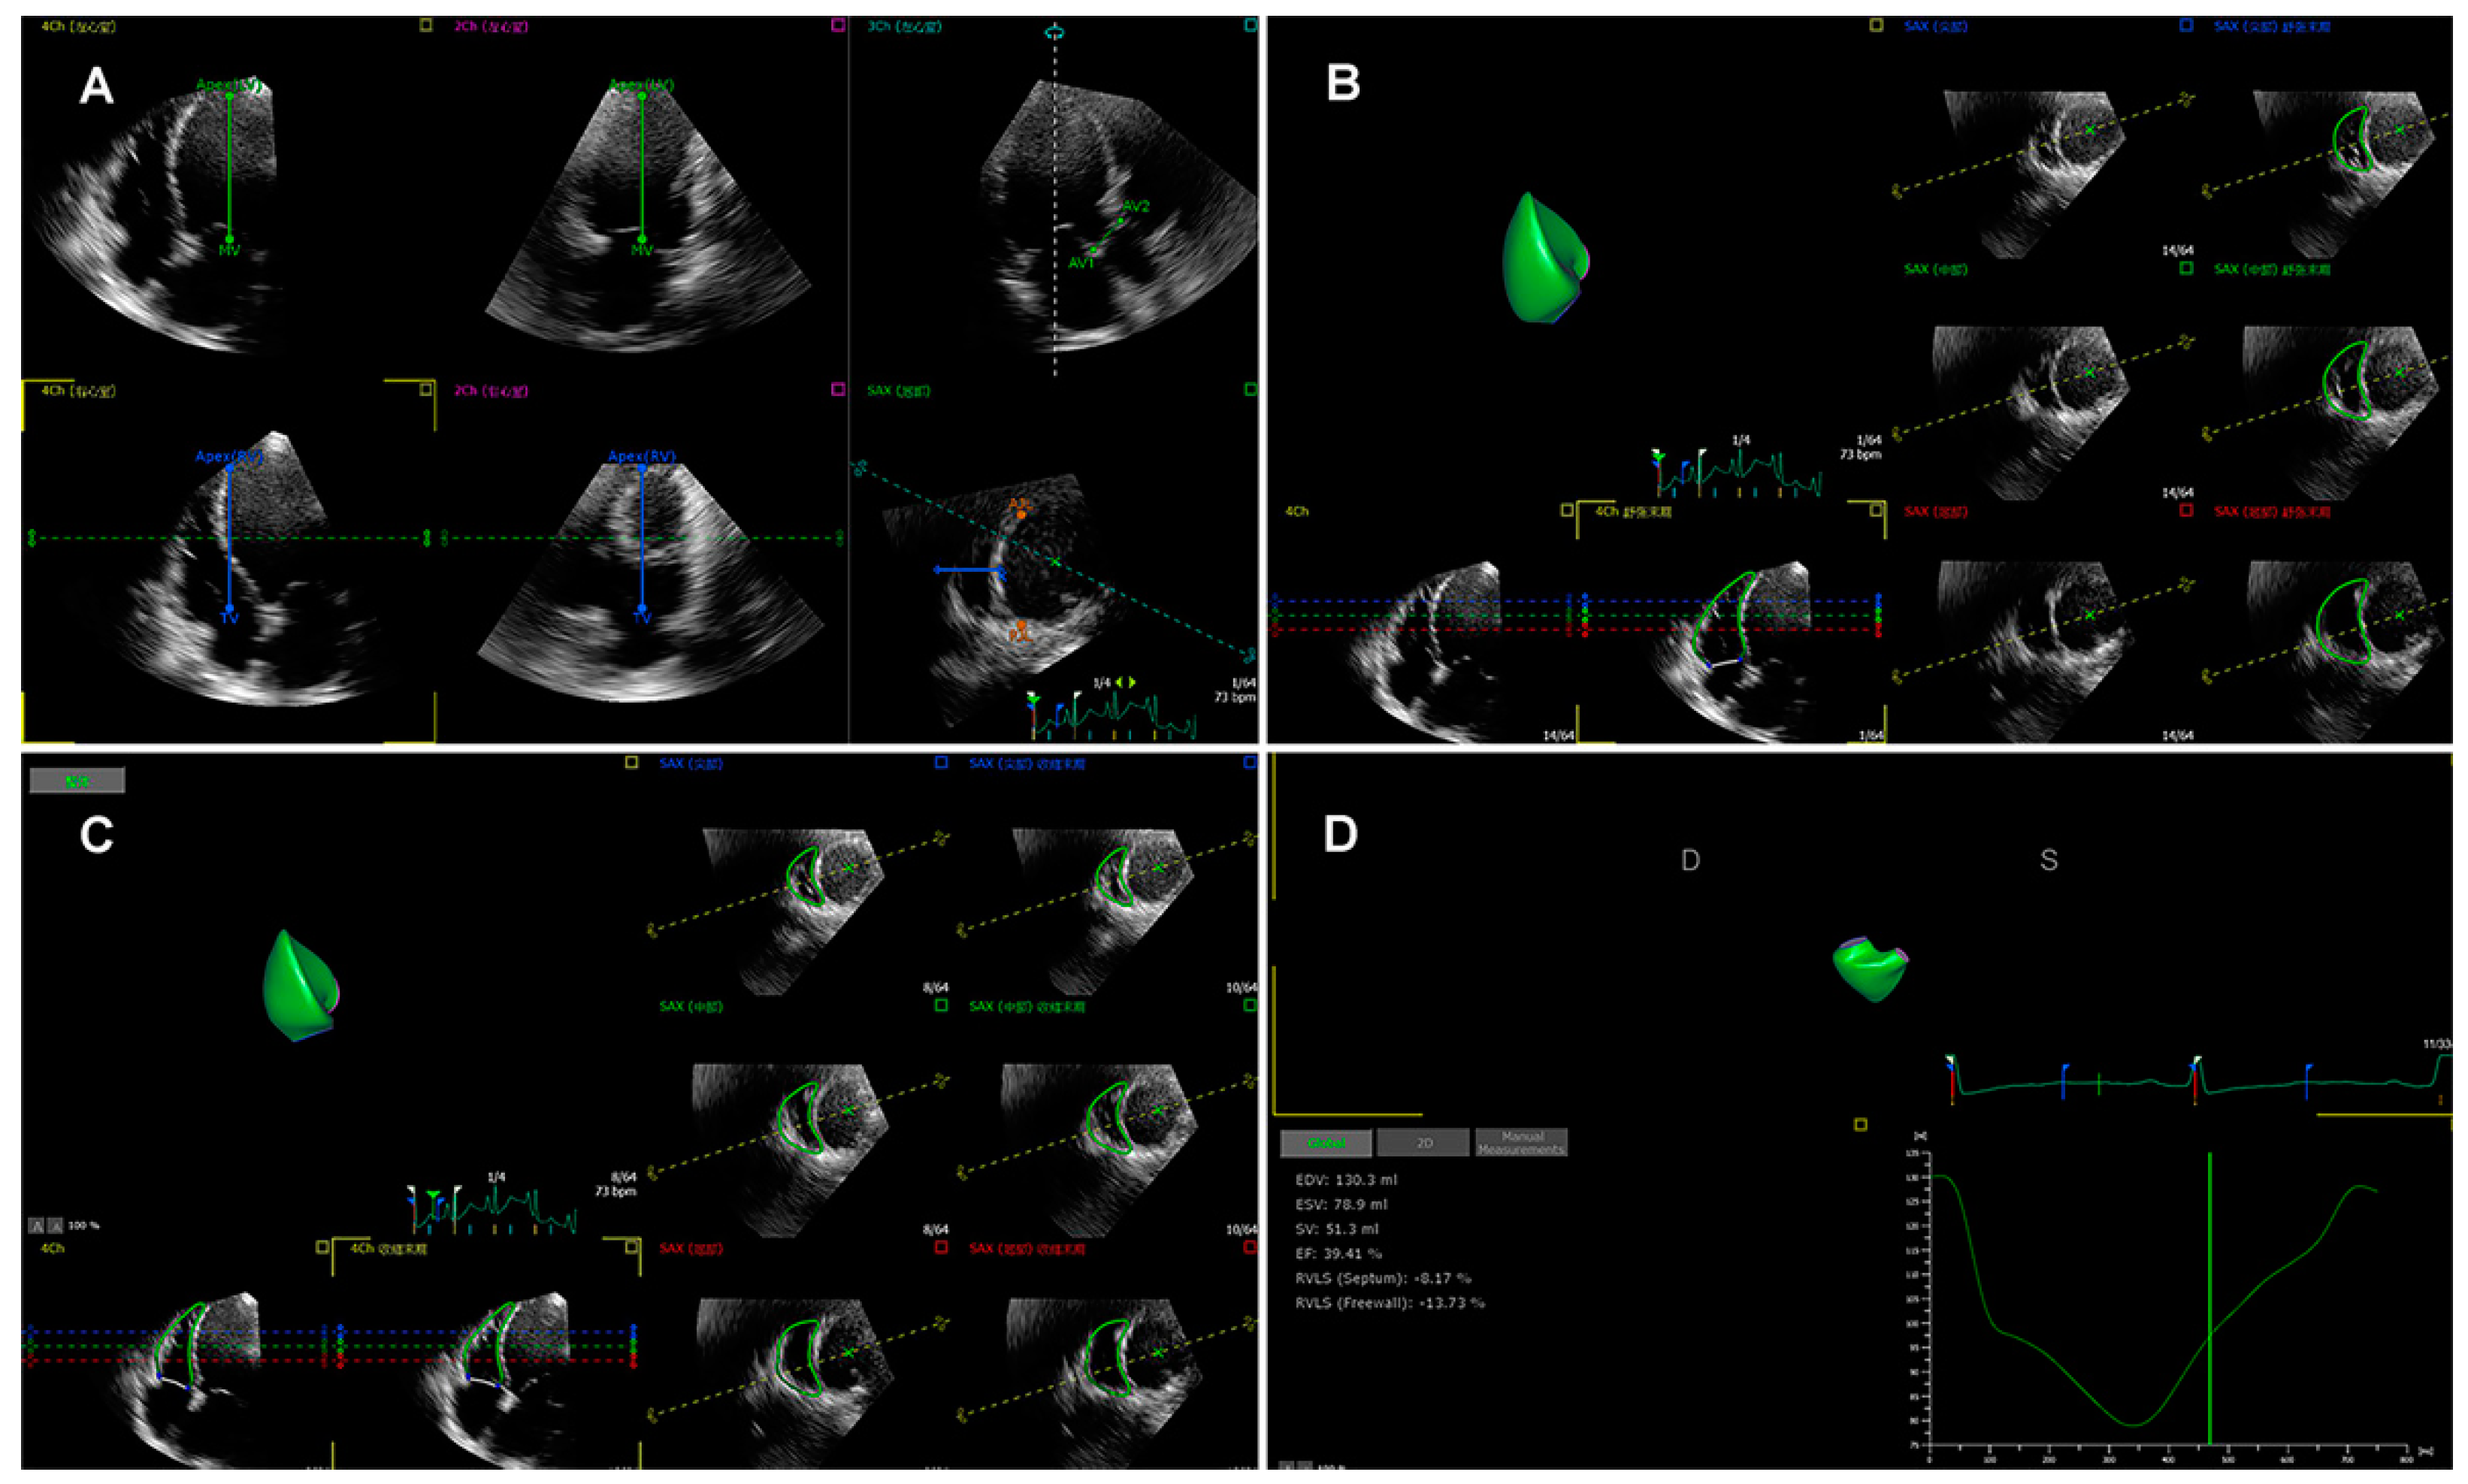

3.3. Three-Dimensional Speckle Tracking Echocardiography

- Li, Y.; Zhang, L.; Gao, Y.; Wan, X.; Xiao, Q.; Zhang, Y.; Sun, W.; Xie, Y.; Zeng, Q.; Chen, Y.; et al. Comprehensive Assessment of Right Ventricular Function by Three-Dimensional Speckle-Tracking Echocardiography: Comparisons with Cardiac Magnetic Resonance Imaging. J. Am. Soc. Echocardiogr. 2021, 34, 472–482. [Google Scholar] [CrossRef]

- Li, Y.; Wan, X.; Xiao, Q.; Zhang, Y.; Sun, W.; Xie, Y.; Zeng, Q.; Sun, Z.; Yang, Y.; Wang, J.; et al. Value of 3D Versus 2D Speckle-Tracking Echocardiography for RV Strain Measurement: Validation with Cardiac Magnetic Resonance. JACC Cardiovasc. Imaging 2020, 13, 2056–2058. [Google Scholar] [CrossRef] [PubMed]

- Tian, F.; Zhang, L.; Xie, Y.; Zhang, Y.; Zhu, S.; Wu, C.; Sun, W.; Li, M.; Gao, Y.; Wang, B.; et al. 3-Dimensional Versus 2-Dimensional Speckle-Tracking Echocardiography for Right Ventricular Myocardial Fibrosis in Patients with End-Stage Heart Failure. JACC Cardiovasc. Imaging 2021, 14, 1309–1320. [Google Scholar] [CrossRef] [PubMed]